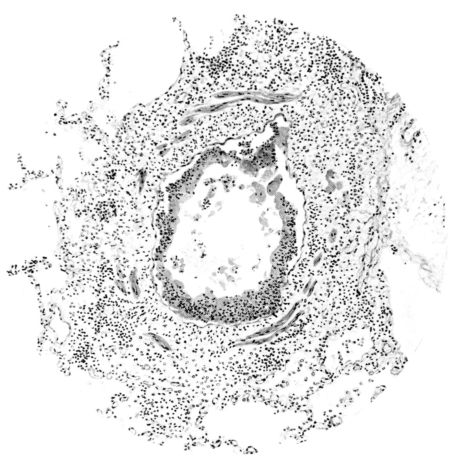

FIG. III. AUTOPSY NO. 90. DRAWING FROM A LESION OF THE TRACHEA (SOMEWHAT OLDER THAN THAT ILLUSTRATED IN FIGURE II). THE MUCOSA IS ENTIRELY LACKING. CONGESTION AND EDEMA ARE THE STRIKING FEATURES IN THE SUBMUCOSA. THE NECROTIZING PROCESS HAS EXTENDED INTO THE MUCUS GLANDS. THIS IS SHOWN IN THE LOWER PICTURE.

The changes are less marked, perhaps, in the trachea than in its finer ramifications. The mucosa is constantly more or less destroyed and large areas, usually focal, are entirely devoid of their epithelial covering. This is replaced by a sparse exudate, composed largely of red blood cells, mucus, a small amount of fibrin, and nuclear fragments (Fig. II). It may dip into the submucosa for a short distance, but usually these indentures are associated with the ducts of the mucous glands into which the inflammatory reaction extends. A more striking feature than the exudate, however, is the edema and the congestion of the submucosa. The loose areolar tissue of the submucosa is spread widely apart, and throughout it distended blood vessels are very conspicuous. Occasionally such a vessel is broken and actual hemorrhage appears in the submucosa. Occasionally, too, the inflammation extends down the duct to the mucous gland itself, and here, also, aplastic inflammatory reaction is evident, inasmuch as the acini now stain intensely red with the cells undifferentiated from each other and specked here and there by broken remains of the dead nuclei (Fig. III). After the disease has continued for a short period, even at the end of five or six days, some regeneration of the epithelial lining may be seen (3) (Fig. IV). But despite this, the acute picture persists, and there goes on, side by side, an attempted repair characterized by epithelial regeneration and the same evidence of acute change. Since the lesion is essentially a superficial one, scars or contractures of any extent are not encountered in the trachea, even in examples of the disease that have ended fatally only after many weeks.[4]